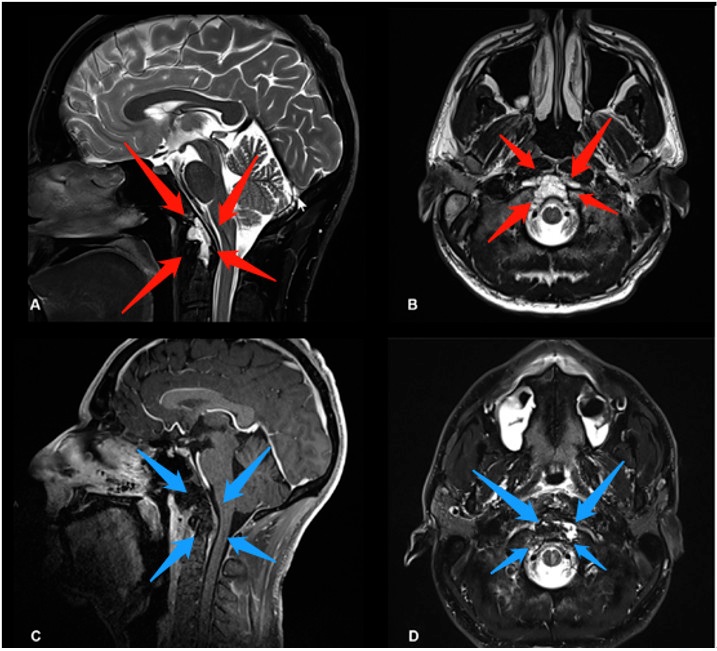

术前(红色箭头):A、B图显示位于右海绵窦中心的脊索瘤病变。病变集中在右侧海绵窦和翼骨上,并在右侧邻卵圆孔。

手术过程:神经内镜单鼻孔经蝶窦手术切除

术后(蓝色箭头):C图表示矢状位显示无肿瘤残余。D、E、F图显示轴位、冠状位脊索瘤被绝大部分切除。